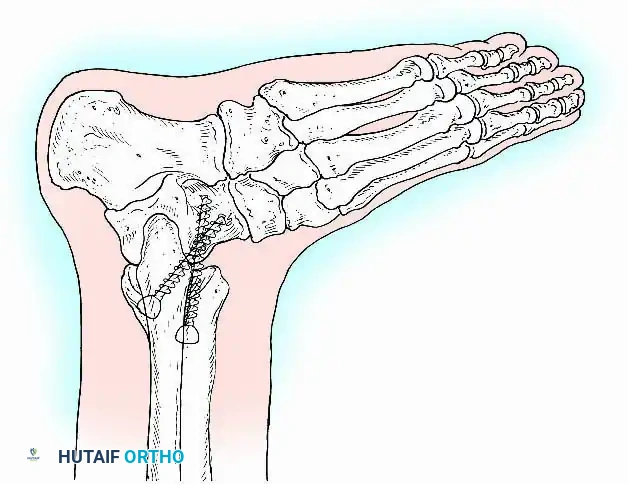

Internal fixation is currently the preferred method for uncomplicated ankle arthrodesis due to higher union rates, superior patient comfort, and the elimination of pin-tract infections. Biomechanical studies demonstrate that crossed, large-diameter (6.5 mm or 7.3 mm) cannulated cancellous screws provide exceptional resistance to shear and torsional forces.

A standard construct involves two or three screws:

1. A "home run" screw directed from the posterior malleolus into the anterior neck of the talus.

2. A screw from the medial malleolus into the lateral body of the talus.

3. A screw from the anterolateral tibia into the medial talar body.

In cases of severe osteopenia or when extending the fusion to the subtalar joint (Tibiotalocalcaneal Arthrodesis), retrograde intramedullary nailing provides a load-sharing construct with superior bending stiffness.